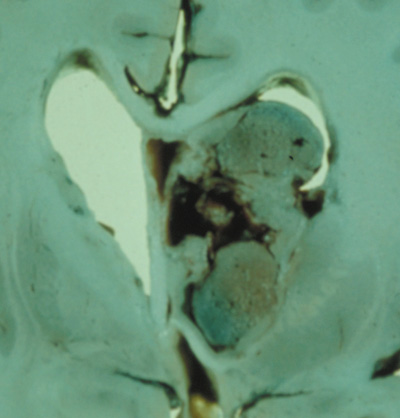

1. Superficial cortical sclerosis (parenchymal hamartoma) which distort the gyri. Microscopy shows large atypical fibrillary type astrocytes with few associated neurons and areas of calcification.133 The numerous abnormal glial processes and fibers make the tissue abnormally firm or “sclerotic” on palpation (Fig. 13).132

Fig. 13. Tuberous Sclerosis Complex: “cortical sclerosis.” Numerous abnormal glial processes make the tissue abnormally firm or “sclerotic” on palpation.132